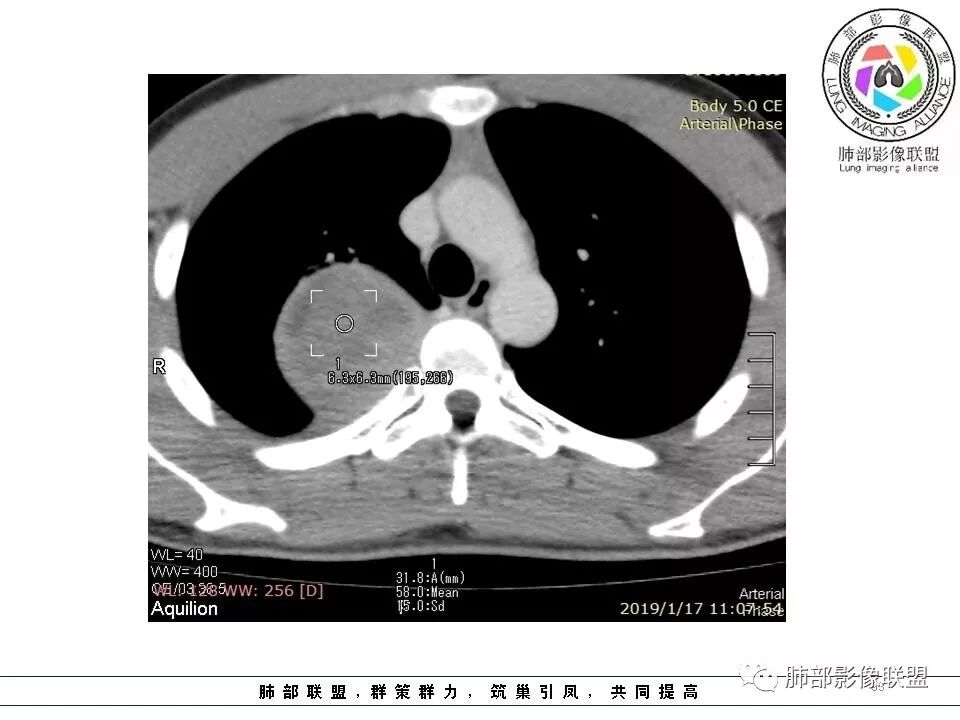

右后纵膈脊柱旁软组织占位,形态规则类圆,边缘光整,肺组织受压,胸膜尾,肋间动脉供血。中度不均匀延迟强化。

后纵隔脊柱旁占位性病变,疾病谱有神经鞘瘤,sft,节细胞瘤,髓外造血。此例有胸膜尾征,蛇纹征 ,延迟强化。考虑胸膜孤立性纤维瘤。看到有供血动脉,但不知道是哪里的血管。

右后纵膈脊柱旁软组织占位,边界清晰,光整,肺组织受压。胸膜被掀起,肋间动脉供血,中度不均匀延迟强化。考虑神经鞘瘤,不除外纤维瘤

右后纵膈脊柱旁软组织影,与纵隔结构分界不清,形态规则类圆,边缘光整,肺组织受压,胸膜尾,肋间动脉供血。肺动脉推移,中度不均匀延迟强化。考虑神经来源,神经鞘瘤,神经纤维瘤二者不易鉴别。

青年男性,间断胸痛;右侧脊柱旁可见一类圆形软组织密度影,密度欠均匀,增强扫描呈轻中度持续强化,邻近肺组织及肺动脉推移,可见肋间动脉供血,部分胸膜下脂肪可见,部分层面似见与右侧椎间孔相连。考虑后纵隔神经源性肿瘤。

病灶定位脏层胸膜,肺组织受挤压,有胸膜尾征,动脉期可见血管支配,考虑肺动脉供血,静脉期,强化增强明显,符合快进慢出特点,病灶内可见低密度区,考虑胸膜孤立纤维瘤。

年轻患者,偶胸痛,巨大肿块,无明显纵膈淋巴结肿大,无明显胸腔积液,考虑良性或低度恶性肿瘤。30.8-44-58-61hu,渐进性强化,边缘光滑,平扫密度不均,增强密度不均,纤维可以渐进性强化,不强化(或低密度去)区,为粘液。考虑孤立性纤维腺瘤伴粘液。

1.右上胸内脊柱旁类圆形肿块,质地似乎比较坚实,密度稍显不均,但未显示明确的坏死。

2.肋间动脉病供血也提示肿块来自后纵隔?

4.静脉期轻度不均匀强化,注意不是环形强化,亦未见明确的“AB区”,这点也不支持神经鞘瘤。临床及病灶轻度强化都不支持副节瘤。